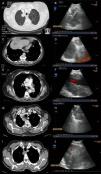

En la figura 1 se muestran algunos ejemplos representados por sus imágenes de tomografía computarizada y ecoendoscópicas.

Ejemplos de imágenes radiológicas y sonográficas de 4 de los casos de la serie.

A y B: Imágenes de tomografía computarizada (TC) y ecoendoscópica de una masa localizada en el lóbulo superior derecho puncionada por ecobroncoscopia, con resultado de adenocarcinoma de origen pulmonar. C y D: Imágenes de TC y ecoendoscópica de un paciente con una lesión pulmonar en lóbulo inferior izquierdo y una adenopatía en la estación mediastínica 9 derecha, puncionadas ambas por ecobroncoscopia a través del esófago con resultado en las 2 de metástasis de carcinoma de colon. E y F: Imágenes de TC y ecoendoscópica de una masa hiliar izquierda que engloba la arteria pulmonar con punción guiada por ecobroncoscopia diagnóstica de adenocarcinoma de origen pulmonar. G y H: Imágenes de TC y ecoendoscópica de una masa paratraqueoesofágica derecha de posible origen en el lóbulo superior derecho con diagnóstico tras punción realizada a través del esófago de adenocarcinoma de origen pulmonar. I y J: Imágenes de TC y ecoendoscópica de una masa localizada en el lóbulo superior derecho que infiltraba mediastino puncionada por ecobroncoscopia, con resultado de adenocarcinoma de origen pulmonar.